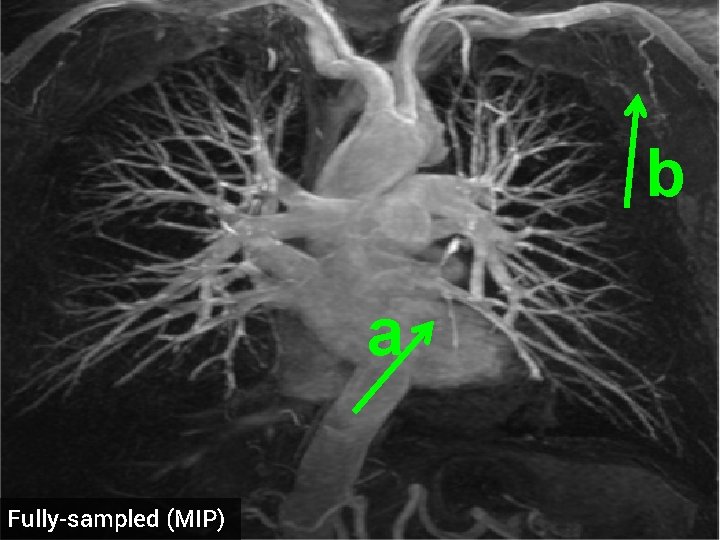

3 -D Compressed Sensing MRA § 512 x 76 voxel MRA dataset obtained from physiobank (see ref. [6]) § Simulated single coil acquisition § Retroactively undersampled at 1. 5 -fold acceleration § Random Gaussian sampling of k-space § 5 d. B additive Gaussian noise § Optimized regularization parameter MIP of original MRA dataset

b a Fully-sampled (MIP)

b a TV recon, 1. 5 x accel. (MIP) SNR = 14. 53 d. B

b a HDTV 2 recon, 1. 5 x accel. (MIP) SNR = 15. 11 d. B

a Fully-sampled (MIP)

a TV recon, 1. 5 x accel. (MIP) SNR = 13. 87 d. B

a HDTV 2 recon, 1. 5 x accel. (MIP) SNR = 14. 23 d. B